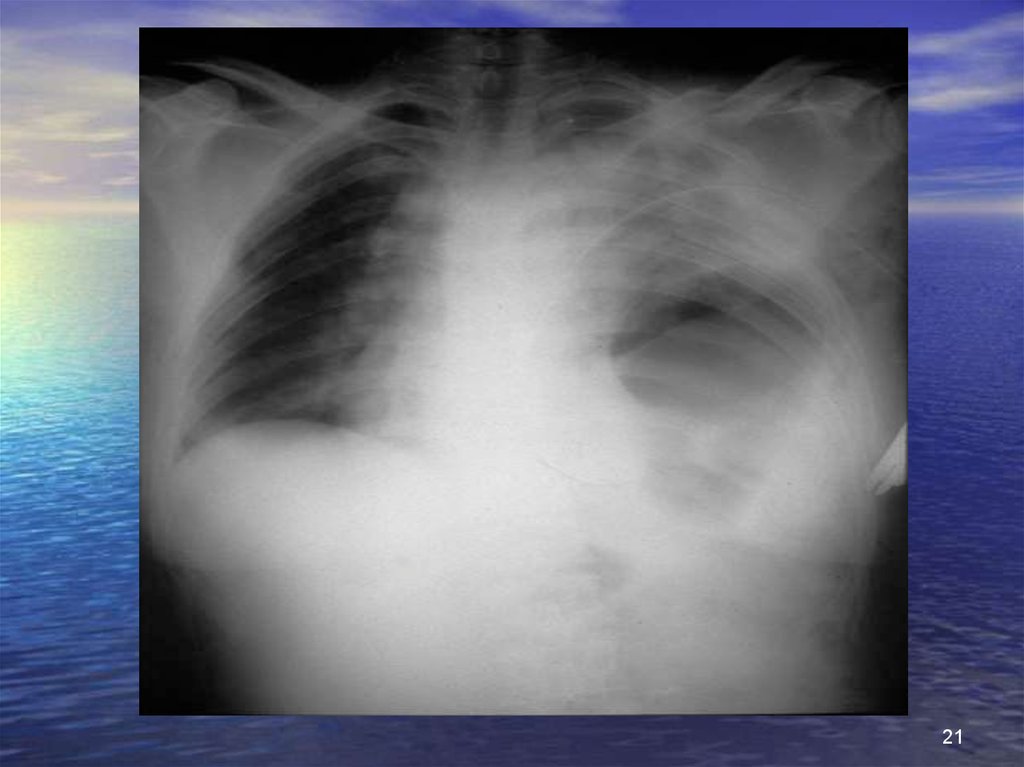

21.

21